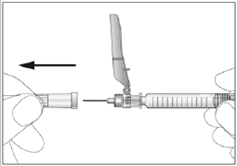

11. Ziehen Sie das Schutzschild von der Nadel weg in Richtung Schaft der Spritze. Das Schutzschild verbleibt in der von Ihnen eingestellten Position (siehe Abbildung 4).

4